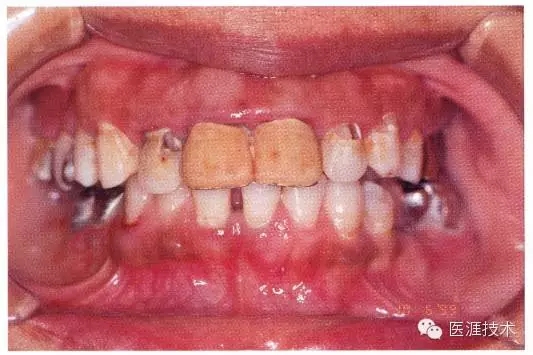

22歲男性牙齦炎的臨床圖像

22歲男性,抽煙(1天約15根,煙齡5年)。刷牙狀態(tài)不佳。抽煙者特有的纖維性牙齦,未見發(fā)紅、腫脹。探針觸診,所有部位均出血。X線牙片未見骨吸收,診斷為牙齦炎。